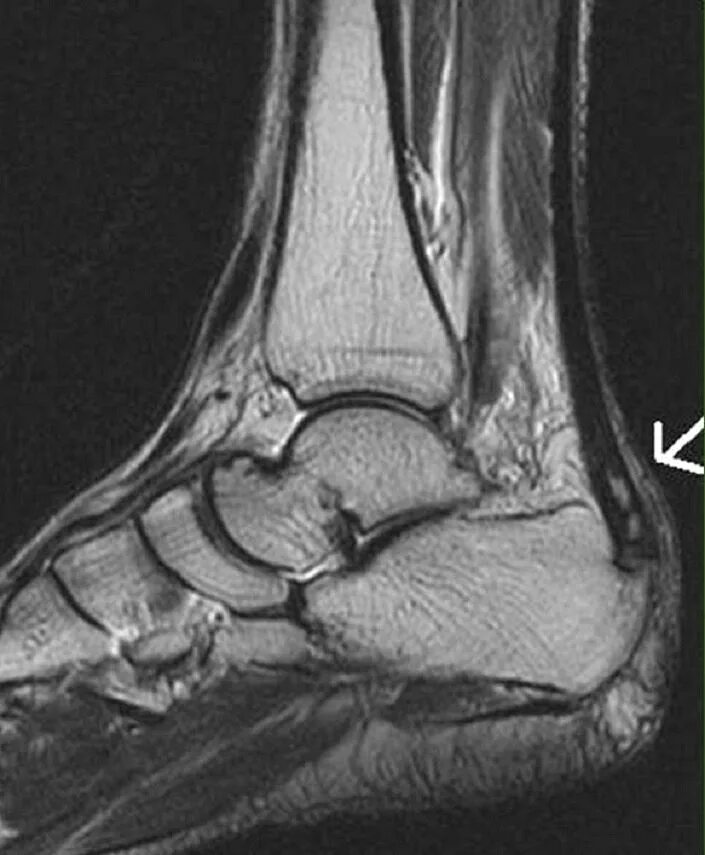

Обызвествление сухожилий мышц